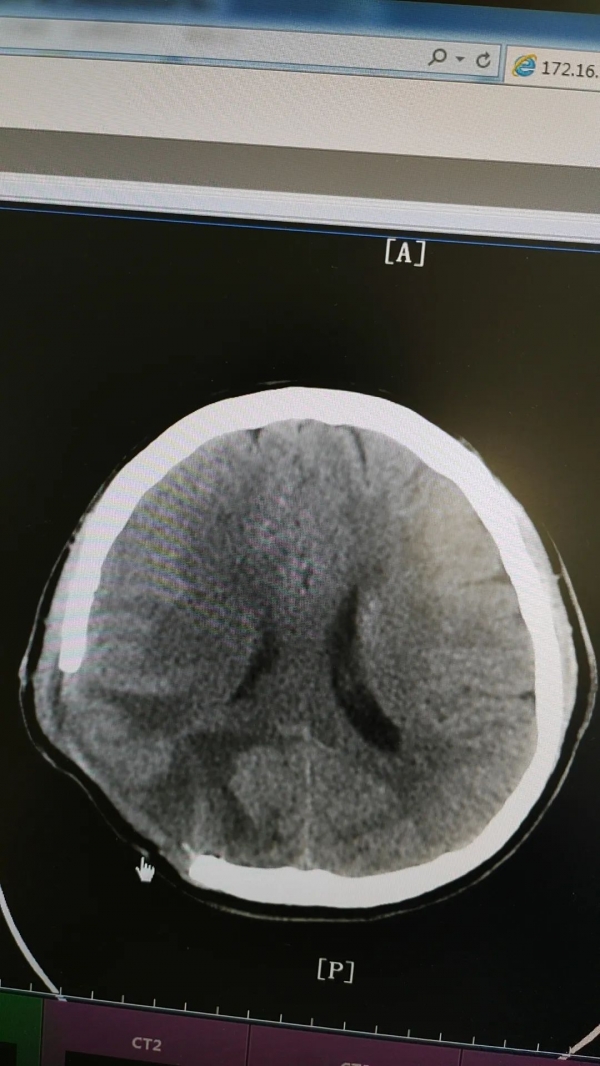

53歲的柴大叔家住湖南長沙,2023年9月工作需要來鄭州出差,出差期間突然頭痛、嘔吐起來,隨即撥打120送至我院急診科,經(jīng)過CT檢查發(fā)現(xiàn),柴大叔右側(cè)頂枕葉腦出血,并有水腫情況,神經(jīng)外科專家張新昌教授立即會診,柴大叔被確診為“腦出血”并收治外一科治療。

腦出血是嚴(yán)重的腦血管疾病,致死率高達(dá)35%以上,易引起偏癱、認(rèn)知障礙、語言障礙等后遺癥。

危急時刻,外一科團(tuán)隊(duì)協(xié)同麻醉科手術(shù)室為核心力量,開通綠色通道,各科室部門快速響應(yīng)整合協(xié)作,制定科學(xué)且可行的方案,全力以赴展開救治。

術(shù)前

術(shù)后